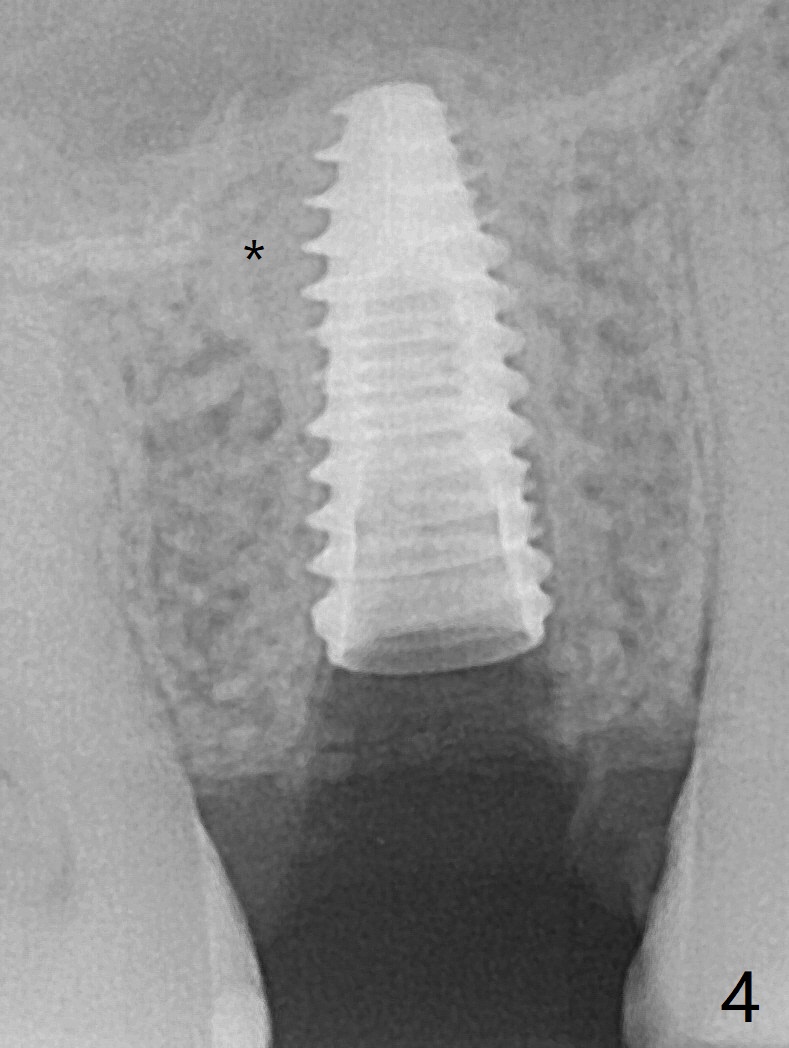

40岁女右上5近中龈下龋齿(图一),要求拔除植牙,上颌窦底板已经破坏穿孔,但是窦膜完整(图二)。清创后,放置PRF膜和粘性骨粉,用挖匙和上颌窦充填器尽量往上面推。然后放置导板,使用2.2x7.3 和3.0x7.3毫米钻头完成钻洞,可能无意中把骨粉推入上颌窦,之后利用报废植体(图三,四)完成提升,同时修补根尖缺损(利用之前放置的骨粉,图四:*,与图五(术前)对比)。当报废植体取出时,植牙窝已经形成,再放入少量骨粉,植入同样大小(之前扭力高)正式植体(不同品牌,图六,七),这时扭力低,放置愈合帽和骨粉(图七,八),以及6-9个月吸收膜,使用牙周胶水固定(图九),最后牙周敷料。术中术后几个小时没有上颌窦膜破裂迹象。术后一周牙周敷料松动,造成不适,去除时,膜好像粘附于敷料一起去除,骨粉暴露(图十),使用树脂敷料固定。后者术后一个月去除,因为局部有臭味。术后4个月切开放置愈合基台(图十一),术后五个月放置修复基台(图十二),使用塑料袖取模。术后5.5月同时放置牙冠和基台,十分顺手,口内粘固,之后同时取出,除去多余粘固剂,然后拧紧30Ncm(厂家推荐35 Ncm),一切非常顺利,觉得拍摄X光片是多余的。美中不足的是开孔(access hole)偏腭侧(图十二;由于自由手植入植体,与设计对比)。